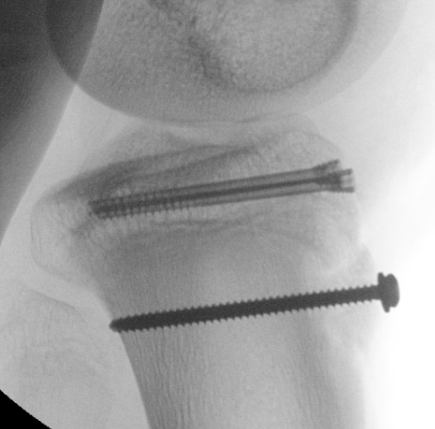

Type I /Type II

Technique

Screw +/- anchor fixation +/- tension band fixation of tibial tubercle and patella tendon

- screw +/- washer in fragment if large

- can supplement with Krackow sutures in patella tendon and fixed distally with suture anchors